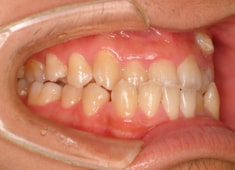

反対咬合+左上3番高位埋伏

(受け口+左上3番目の永久歯が上顎の中に埋まったままはえてきていない)

解説:残存している左上乳犬歯Cを抜歯し、そのスペースに左上3番を誘導しました。Cと犬歯ではスペースが足りないので、前歯をアドバンスさせ、反対咬合を同時に解消しております。

治療前